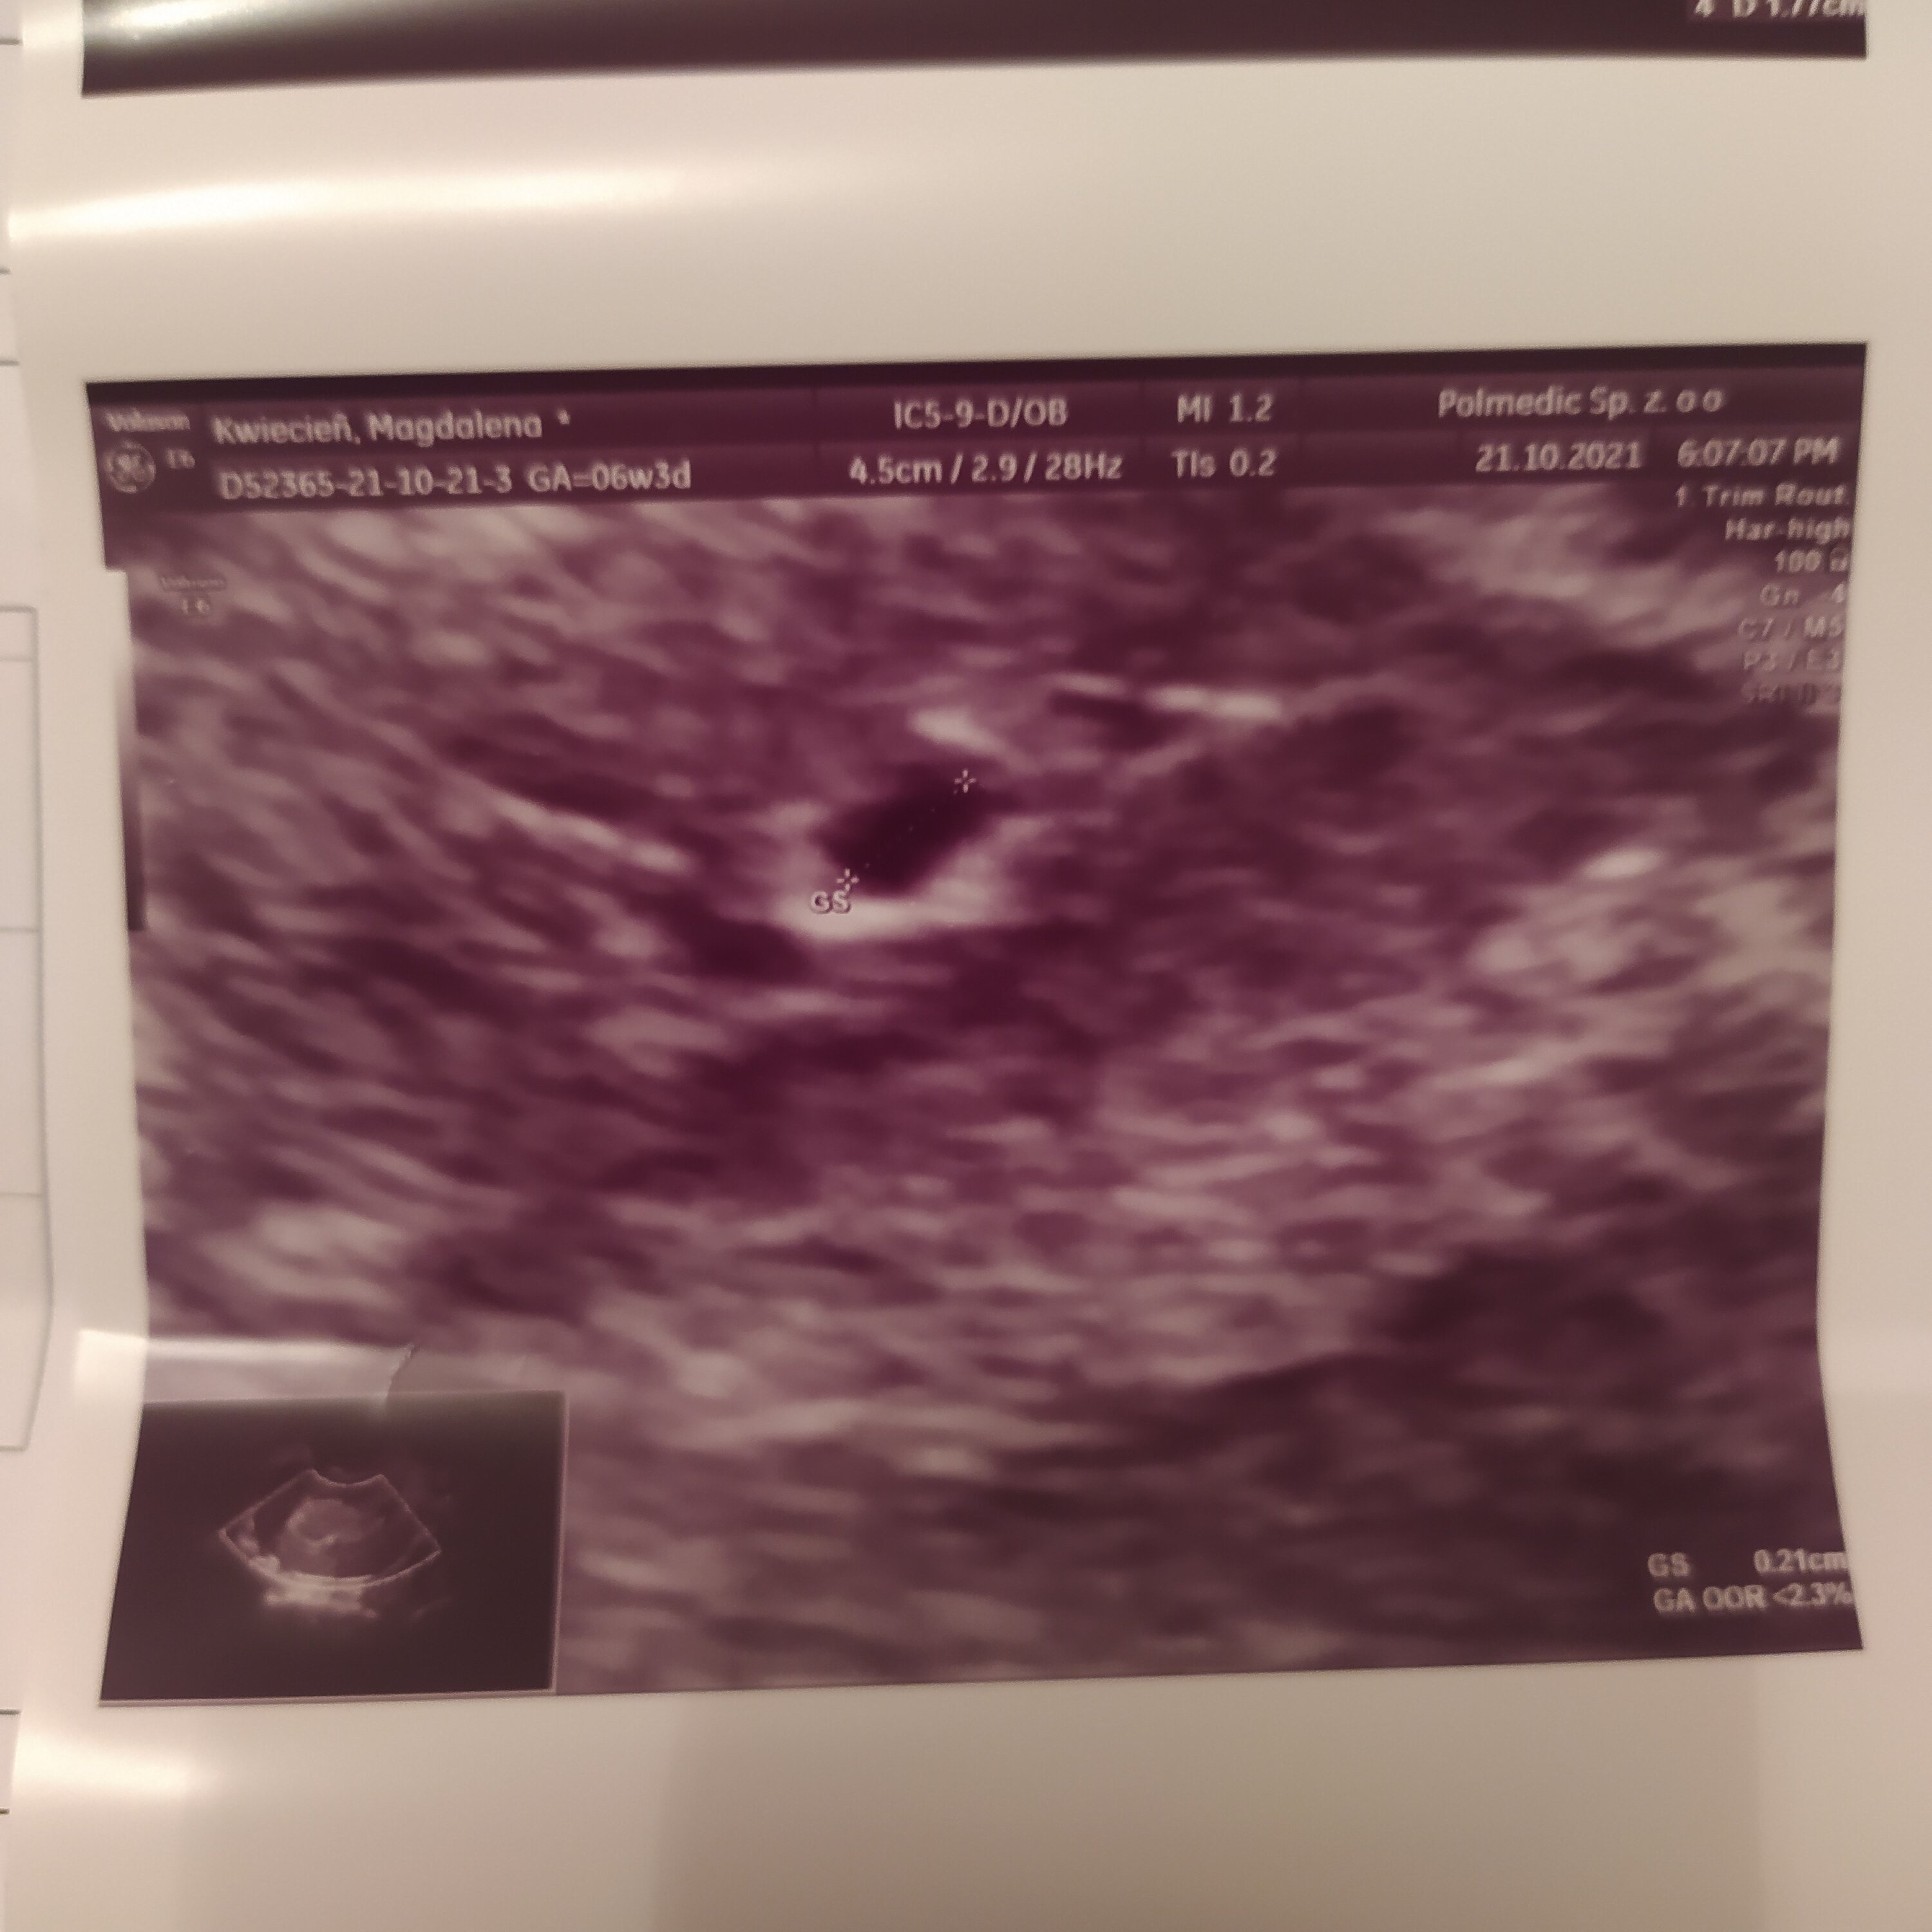

Zdjęcie które dostałam od lekarza

I opis

Załączniki

• IMG_20211021_204825.jpg

IMG_20211021_204825.jpg

540,6 KB · Wyświetleń: 248

• IMG_20211021_204832.jpg

IMG_20211021_204832.jpg

391,9 KB · Wyświetleń: 250

A możesz pokazać zdjęcie? Bo to jest wręcz niemożliwe aby coś było widać na usg. Często pseudo pęcherzyk w macicy widać właśnie przy ciąży pozamacicznej.

Ja mam hcg 7tys. I tylko mam pęcherzyk.. Siostra ma 1000 hcg i nie widać nic jeszcze. Może faktycznie pokaz zdjęcie.